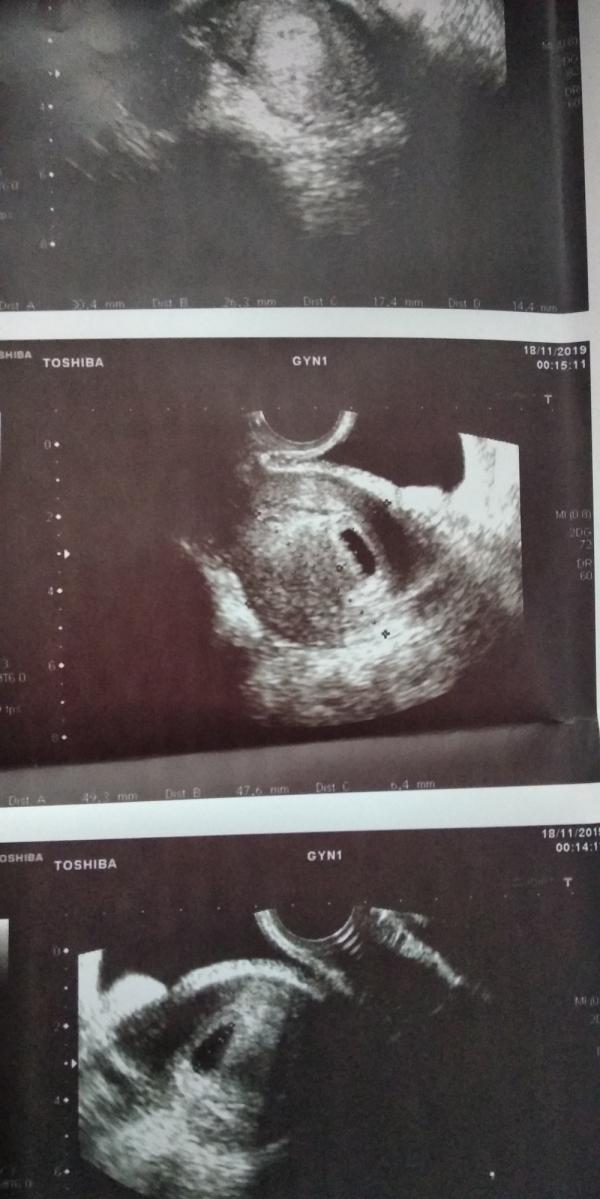

Вчора була в лікаря, робили УЗД, сказали деформація плідного яйця, та загроза, але сказала загроза це гучно сказано. Сказали лежати навіть не вставати, призначили дюфастон і купу ліків. Хтось зтикався з таким діагнозом?

Я. Именно так и было, через неделю всё в норме было. Была небольшая отслойка хориона, деформация из-за тонуса матки. Пила Дюфастон до 13 недель.

Эта деформация из-за тонуса мышц матки и это нормально. Вообще, это только в нашей стране лечат 🤦♀️. Лежать это хорошо, добрые смешные фильмы хорошо смотреть, разговаривать с малышом. Вообще, тонус -это нормально, это матка реагирует на плодное яйцо. Сейчас хорошо валяться, быть в хорошем настроении и позитивчике. У меня была деформация на 5 неделе, угроз не ставили. Сказали поставить 5 дней подряд вибуркол в попу. И быть в позитиве 🤷♀️. Вибуркол-это гомеопатия в принципе, поэтому вреда от него немного. А от кучи лекарств -не факт ....